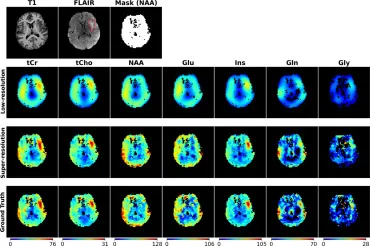

图9. 包含肿瘤的切片中7种代谢物的低分辨率(8×8零填充)、FTDDM超分辨率和真实图像的可视化。第一行显示T1 MRI、FLAIR MRI和NAA的质量过滤掩膜示例。FLAIR中肿瘤由红色虚线描绘。